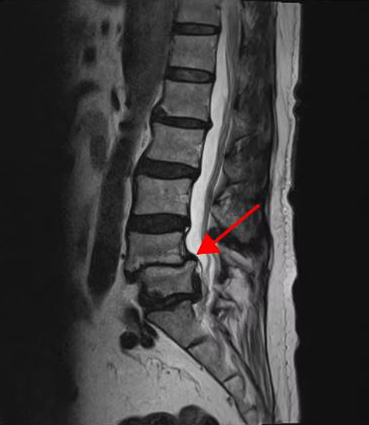

<4-5번 추간공협착증>

<4-5번 척추전방전위증>

이 환자분의 허리 MRI를 보면 4번, 5번 오른쪽에 심한 추간공협착증과 2단계의 척추전방전위증이 있는데, 특히 척추전방전위증 때문에 추간공이 많이 좁아져 있는 상태입니다. 또 왼쪽의 다른 마디에 디스크 파열이 있으나 환자분이 왼쪽으로는 증상이 전혀 없는 것으로 보아 이 디스크 파열은 통증을 일으키지 않는 무증상의 디스크 파열입니다.

이렇듯 4번, 5번 마디의 심한 추간공협착증과 척추전방전위증으로 인해 이 환자분은 다리에 마비가 왔고, 발목에 힘이 빠져 거의 걷지 못하는 상태였습니다. 새벽에 잠에서 깨 화장실을 갈 때는 네 발로 기어갈 정도로 증상이 심했습니다. 신경주사도 많이 맞아봤지만 통증이 전혀 줄지 않아서 결국 수술을 결심하셨는데요. 대학병원을 비롯해 정형외과 및 신경외과 등 아홉 군데 병원에서 진료를 받았지만, 어려운 수술이라고 말하면서 척추유합술, 감압술 등 병원마다 제시하는 수술방법이 다 달라 큰 혼란을 겪으셨습니다. 게다가 수술 후 후유증이나 잔존 증상에 대한 물음에 ‘있을 수도 있고 없을 수도 있다’라는 의사의 말에 수술을 고민하던 중 마지막이라는 생각으로 저희 모커리에 내원하셨습니다.